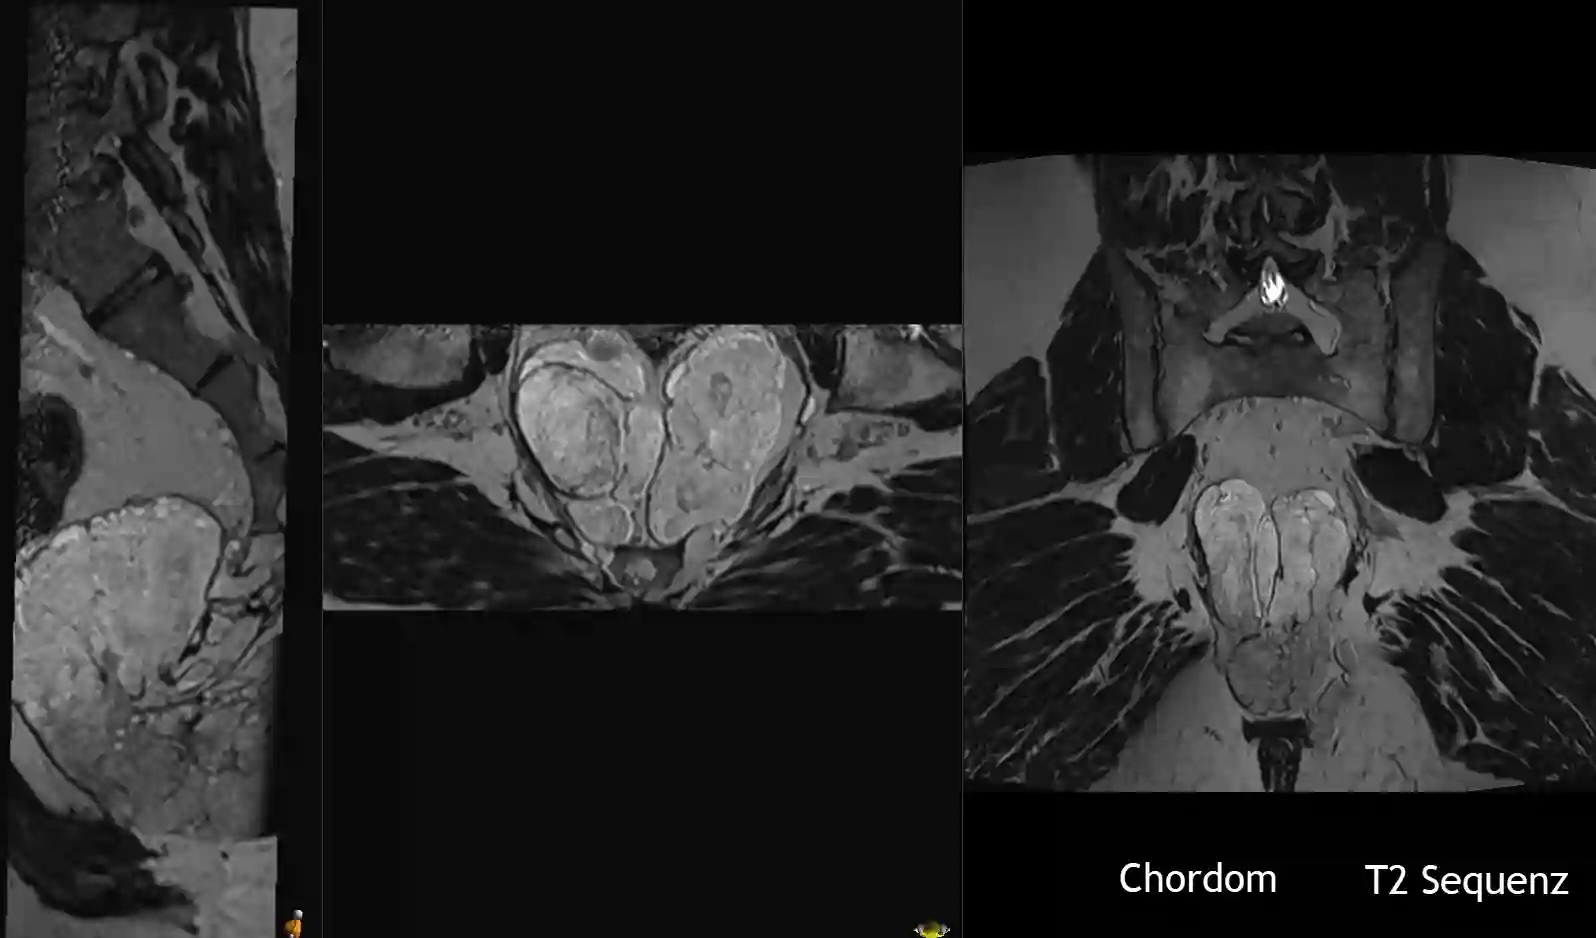

Der Goldstandard bei der Bildgebung von Chordomen ist die MRT-Bildgebung.

MRT

Chordome zeigen sich in der MRT Bildgebung typischerweise wie folgt[^3]:

T1 nativ | T1 mit Kontrastmittel | T2 |

Iso- bis Hypointens | Heterogene Kontrastmittelaufnahme |